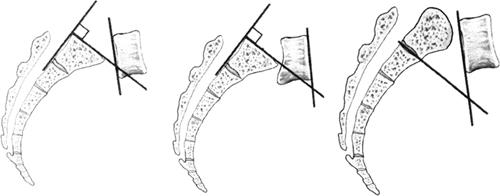

椎间关节(facet joint)(关节突间关节,zygapophyseal joint)属于滑膜关节,由上下相邻关节突的关节面构成。不同节段脊柱其椎间关节的方向也不相同。颈椎椎间关节面平坦,与水平方向成45°角;胸椎椎间关节面也平坦,与水平面成0角,与额面成20°角;腰椎椎间关节上关节面轻度凹陷,下关节面略突,与水平面成0角,与额面成45°角(图1-38、图1-39)。

图1-38 不同椎体节段关节突关节的角度及其平面展示

图1-39 椎间关节的角度